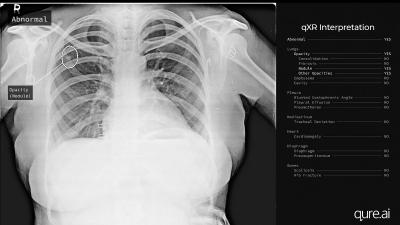

अंकित मोदी की कंपनी ने एक आर्टिफिशियल इंटेलिजेंस तकनीक का आविष्कार किया है। केवल एक मिनट में मस्तिष्क के सीटी स्कैन द्वारा रिपोर्ट करने में सक्षम है।

खास बात यह है कि अंकित और उनके सहयोगियों द्वारा विकसित इस सॉफ्टवेयर को रेडियोलॉजिस्ट की आवश्यकता नहीं है। इस सॉफ्टवेयर का उपयोग अमेरिका, इंग्लैंड, फ्रांस, इटली सहित दुनिया के 20 से अधिक देशों में किया जा रहा है।

ऐसे कई मामले पाए गए हैं जिनमें एक्स-रे में भी रोग के सबसे सूक्ष्म लक्षण मौजूद होते हैं जिन्हें आंखों से पकड़ना मुश्किल होता है, डॉक्टर इस तकनीक की मदद से ऐसे मरीजों को आसानी से पहचानने में सक्षम होते हैं।